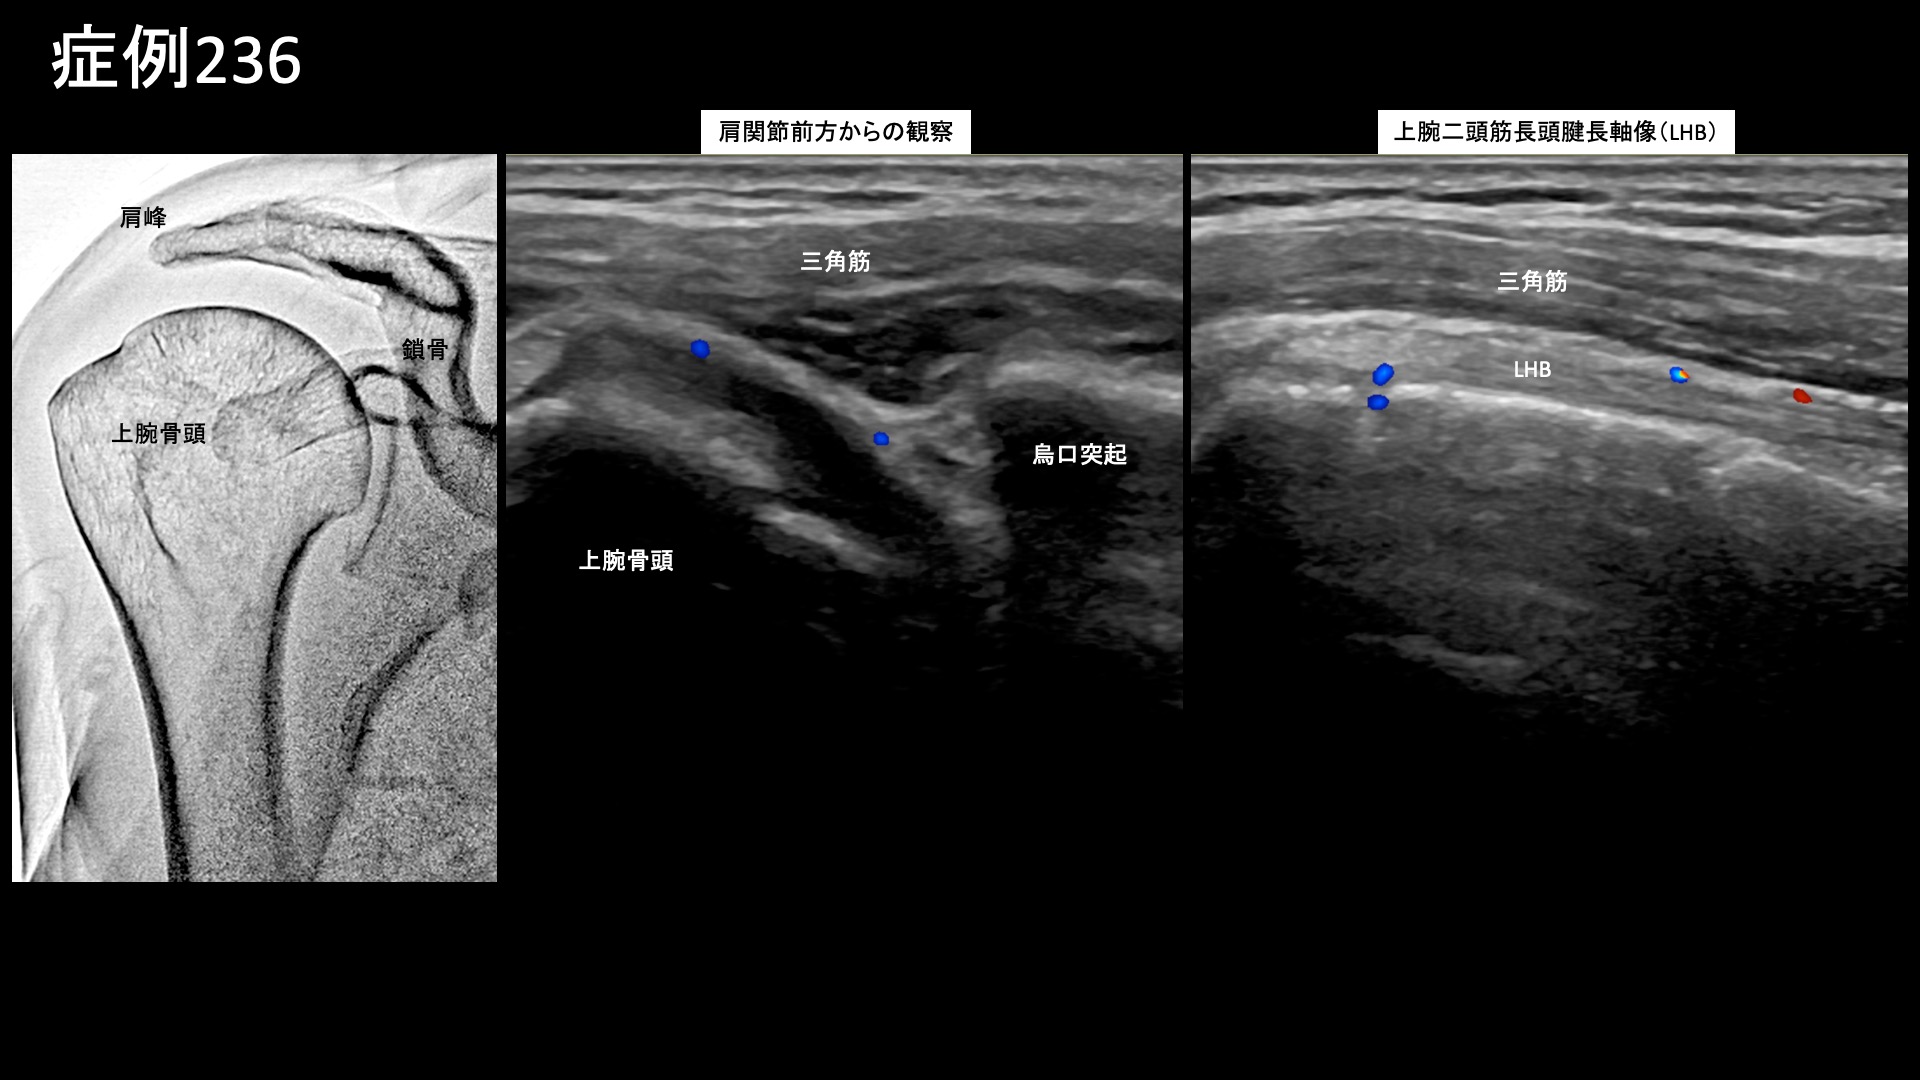

肩:肩こり・四十肩・五十肩 【40代:女性】9ヶ月苦しんだ四十肩の痛みが2週間でほぼ消失・・四十肩後遺症のモヤモヤ血管治療(四十肩、凍結肩、肩関節周囲炎) 2025.09.12 鴨井院長による動画解説 受診までの経過 9ヶ月前から右肩を痛めるようになりました。四十肩と言われリハビリ通院を続けましたが、痛みはひどくなる一方でした。半年くらい経つと痛みが少し緩和されてきて、夜間痛もピークの時よりはおさまりましたが、起床時の痛みが変わらず、可動域制限のため車の運転姿勢も辛い状況でした。少しでも改善すればと思い当院を受診されました。 診察時の所見 右肩関節の可動域を確認すると、外転90度(腕を真横から挙げる動作で水平まで)、外旋15度(腕を外に開く動作が極めて高度に制限)、反対の肩に手を回すことはできず、後ろには腰骨の高さまで回せる程度(結帯動作;L4レベル)でした。レントゲンでは異常はありませんでしたが、エコー検査では、肩関節前方からの観察においてモヤモヤ血管を反映した異常血流信号を認めました。腱板などの明らかな組織損傷は認められず、四十肩後遺症と診断しました。治療適応と判断し、モヤモヤ血管(病的新生血管)に対する運動器カテーテル治療(微細動脈塞栓術)を受けていただきました。 治療の所見 血管造影を行うと、肩甲上動脈、烏口枝などでモヤモヤ血管が濃染像として描出されました。 治療後は画像上速やかに消失しました。その他複数箇所の治療を行い終了しました。 治療後の経過 治療後翌日から改善し、日中の動作が楽になり、窓ふきなどもできるようになりました。治療後2週間、夜間に右を下にして寝ると痛むもののそれ以外の痛みはほぼ消失しました。治療後1ヶ月、普段の痛みは完全に消失しました。可動域も大幅に改善し、外旋動作はほぼ完全に回復しました。反対の肩にも手を回せるようになりました。外転110度と、まだ制限はありましたが、発症9ヶ月経過していることを考えると、回復は非常に順調でした(通常でも、可動域の回復には3ヶ月~6ヶ月程度要します)。近医でリハビリ通院を続けることが可能であることから終診としました。その後も再発することなく過ごせています。 四十肩の詳しい病状説明はこちら 【60代:男性】マラソンランナーを悩ませた繰り返す肉離れによるふくらはぎの痛み(腓腹筋痛症)に対するモヤモヤ血管治療 (腓腹筋痛症、肉離れ後遺症) 前の記事 【90代:女性】ここにできたら要注意!超高齢者に生じた頭部・顔面の帯状疱疹後神経痛(発症1ヶ月) (帯状疱疹後神経痛) 次の記事